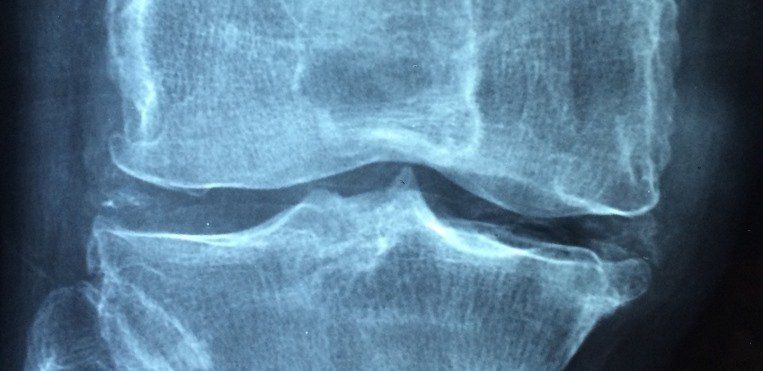

Si llega a darse la situación en la que la persona padece algún dolor o siente crujir alguna de sus articulaciones, lo conveniente, sin lugar a dudas, es consultar a un médico, que, en caso de verlo oportuno, recomendará asistir a un traumatólogo o reumatólogo. En este sentido, uno de los casos en los que puede ser necesario asistir a un médico es cuando se sufre de un desgaste cartilaginoso, ya que se trata de una patología muy relacionada con la artritis. Ésta se desarrolla de forma paulatina y se manifiesta, generalmente, posteriormente a la primera etapa de evolución. El problema que se genera reside en que el cartílago existente entre una articulación y otra alcanza un cierto deterioro que, a su vez, origina una hinchazón que dificulta el buen uso de la articulación afectada. Muñecas, rodillas, hombros, cosos y tobillos son las partes del cuerpo que más posibilidades tienen de presentar daños en los cartílagos.